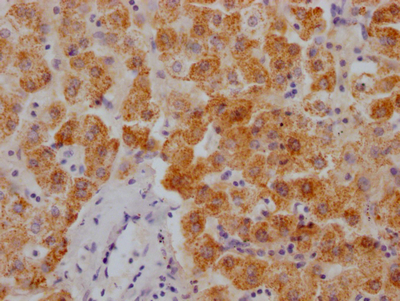

Immunofluorescent analysis of Hela cells using CSB-PA896901LA01HU at dilution of 1:100 and Alexa Fluor 488-congugated AffiniPure Goat Anti-Rabbit IgG(H+L)

應用范圍:ELISA, WB, IF

推薦稀釋比:

Application Recommended Dilution WB 1:500-1:5000 IF 1:50-1:200 -